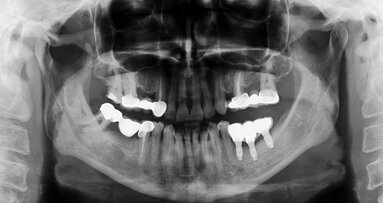

POHANG/SEOUL, South Korea: Guided bone regeneration is widely used for dental implant surgeries. However, in patients with insufficient bone quantity and quality, this approach is less successful and requires a longer treatment period. Depending on the configuration of the defect sites, the use of barrier membranes alone to prevent the ingrowth of non-osteogenic cells is not sufficient to significantly facilitate bone regeneration. Therefore, researchers from South Korea have developed an osteogenic barrier coating material that is expected to improve the success rate of implant treatment, regardless of the bone quality of the implant site.

Guided bone regeneration maintains the space for bone to grow and prevents non-osteogenic cells, such as fibroblasts, from populating the bone defect site, allowing the bone to grow without interference. Even though titanium mesh, one of the most commonly used membranes for guided bone regeneration, performs well and is biocompatible, it can be susceptible to soft-tissue ingrowth through its pores. Therefore, the joint research team from Pohang University of Science and Technology (POSTECH), Kyungpook National University in Daegu in South Korea and Korea University Anam Hospital in Seoul developed a coating material to accomplish reliable clinical outcomes using guided bone regeneration.